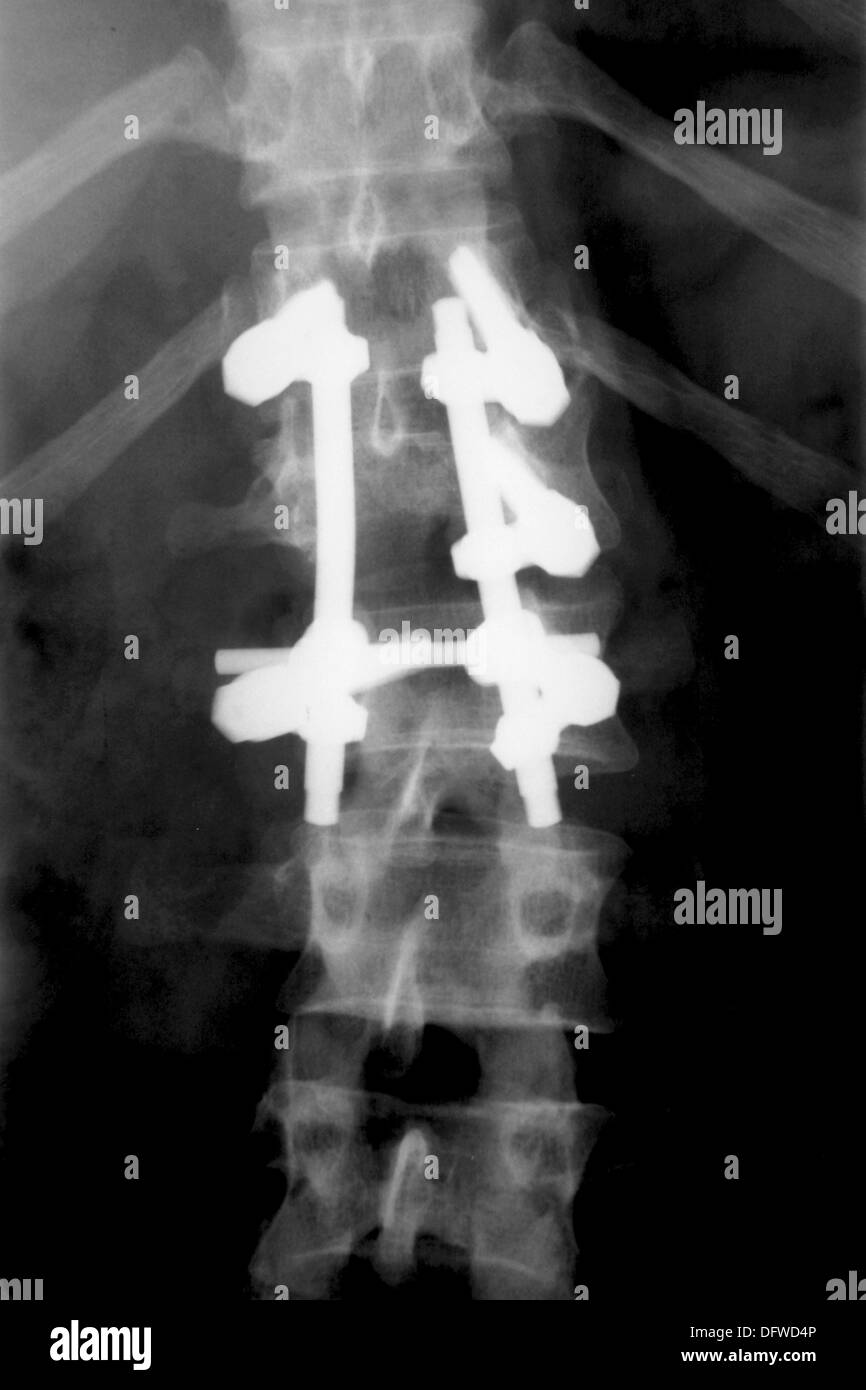

From www.alamy.com

Titanium fixations on spine, compression fractures caused by car Can A Car Accident Cause A Spinal Compression Fracture Even if you need surgery to repair your broken. Spinal fractures are usually caused by osteoporosis or traumas like car accidents. Recovering from a spinal compression fracture requires a careful balance of rest, therapy, and avoiding activities that can. This could include falls, car accidents or other types of physical trauma. Car accidents are a rising trend in spine injuries.. Can A Car Accident Cause A Spinal Compression Fracture.

Titanium fixations on spine, compression fractures caused by car Can A Car Accident Cause A Spinal Compression Fracture Compression fractures can also be caused by trauma, such as a car accident or fall. Car accidents are a rising trend in spine injuries. Even if you need surgery to repair your broken. In such cases, the force exerted on. Spinal fractures are usually caused by osteoporosis or traumas like car accidents. Recovering from a spinal compression fracture requires a. Can A Car Accident Cause A Spinal Compression Fracture.

Titanium fixations on spine, compression fractures caused by car Can A Car Accident Cause A Spinal Compression Fracture In such cases, the force exerted on. This could include falls, car accidents or other types of physical trauma. These types of fractures are more common in younger individuals or those with healthy bones. Even if you need surgery to repair your broken. Acute trauma, such as a fall, car accident, or sports injury, can lead to spinal compression fractures.. Can A Car Accident Cause A Spinal Compression Fracture.